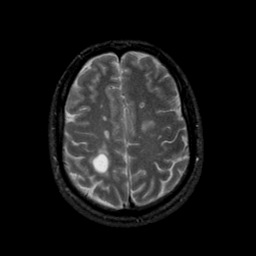

MR Study #9, April 14, 1991 -- Slice #37